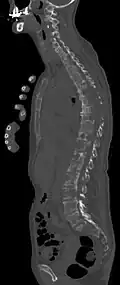

- Vergleich CT / MRT bei osteolytischen Metastasen eines Mammakarzinoms in der Wirbelsäule

Sagittal rekonstruierte CT, Darstellung im Knochenfenster. Da die Patientin multiple Metastasen in allen Körperregionen hatte, konnte sie die Arme nicht für die Untersuchung nach oben nehmen, weshalb die Hände mit abgebildet sind. -

Sagittal rekonstruierte CT, Weichteilfenster. Neben den Metastasen in der Wirbelsäule, die teilweise nach hinten in den Spinalkanal einwachsen, auch Metastasen im Brustbein. Zusätzlich Lebermetastasen. -